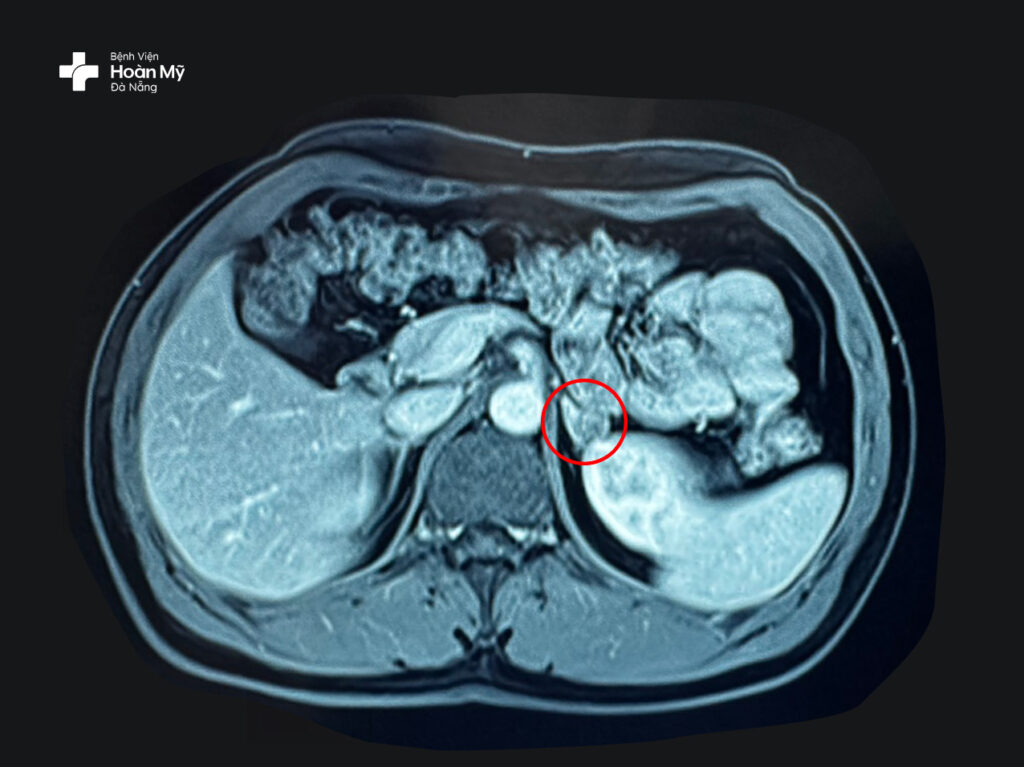

Các bác sĩ khoa Ngoại Tiết niệu – Nam khoa nhận định khả năng cao mỏi yếu cơ, hạ kali máu là biến chứng của bệnh lý này. Kết quả chụp MRI cho thấy có khối u trái, kích thước 12x16mm

Hình ảnh khối u tuyến thượng thận nhỏ được thể hiện rõ trên MRI